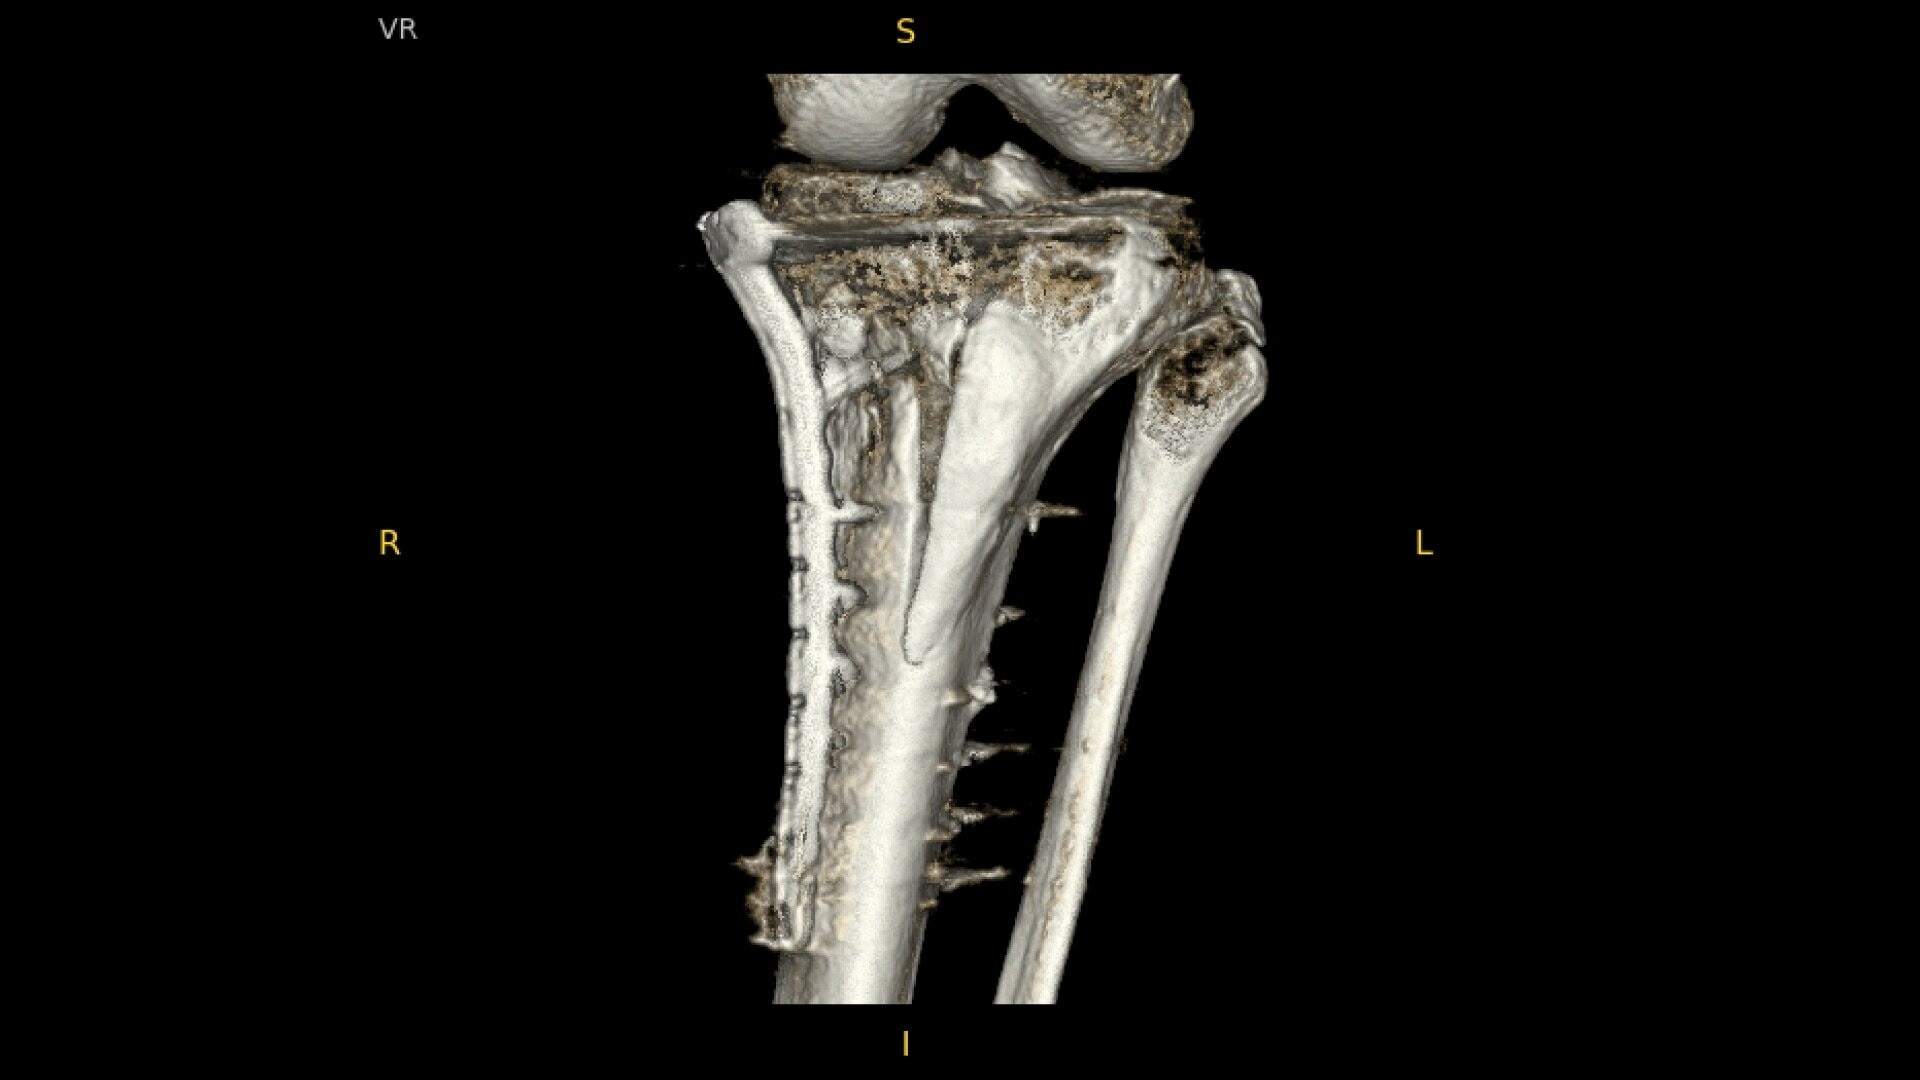

• Pilon fracture fixation

Complex orthopedic procedures require powerful imaging systems. OEC premium C-arms perform in a variety of procedures such as:

See precise anatomical detail of varying densities such as bone and soft tissue with a high dynamic range with the OEC Elite CFD with a flat detector, image processing advancements and 4K viewing display.

OEC C-arms provide orthopedic imaging with a large field of view optimized to clearly visualize orthopedic anatomy, such as the entire long bone femur or minute fractures in extremities. A clear display with comfortable viewing can easily show AP and lateral views, enabling efficient procedure planning.